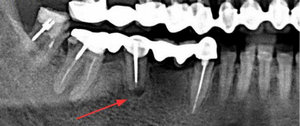

Вопрос с 6 зубом сверху слева. Доктора сначала сказали, что к удалению оба зуба (5 и 6), т.к. между ними воспаление, но потом решили 6 оставить, может восстановится.

Изначально планировала закрывать эти три зуба (4, 5, 6) мостом, поэтому сделали рентген. Боли в них не было. 5 зуб уже удалила, но еще и с 4 при удалении откололся кусок, поставили пломбу.

Смело удаляйте 6 зуб и даже не думайте о мостовидном протезе. Помимо воспаления на корнях у данного зуба может иметься атрофия кости.

Так что удаляйте и через 3-4 месяца необходимо провести операцию синус-лифтинг с последующей имплантацией.